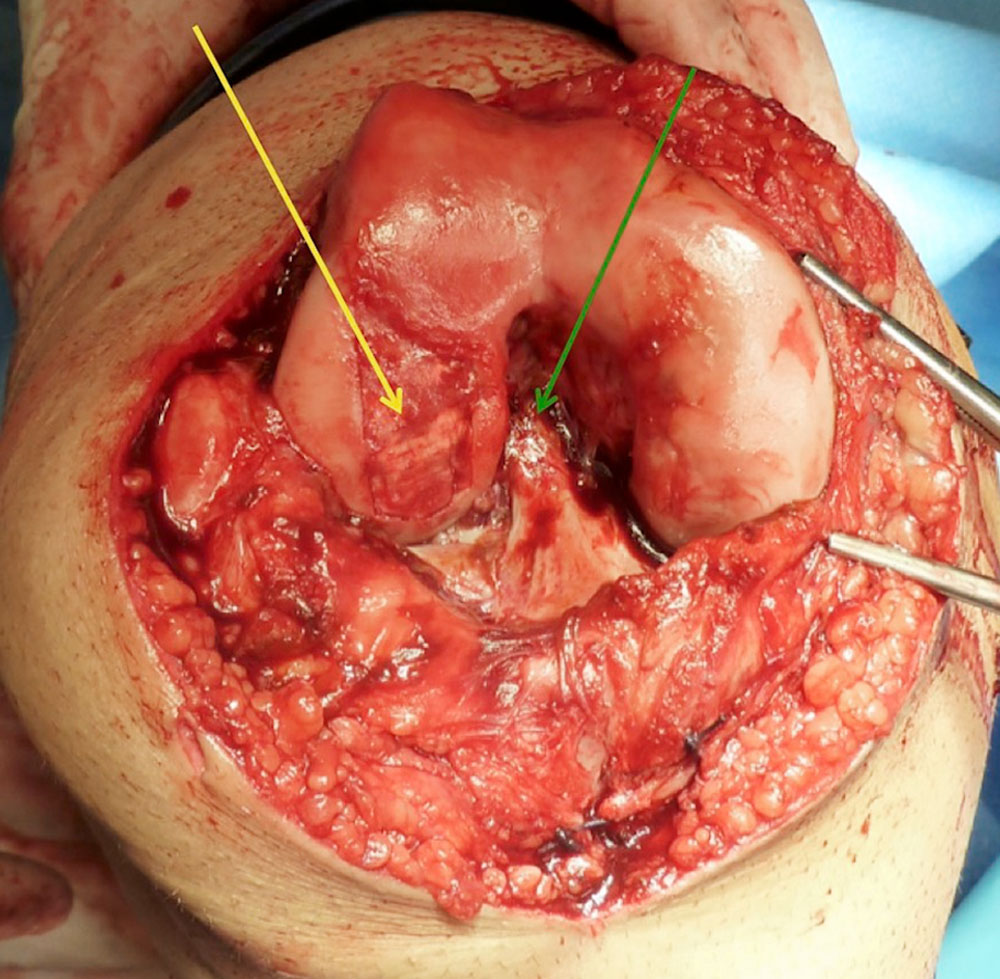

Treatment should always be interdisciplinary. On the one hand, it requires interventional therapy of the peri-articular, or if possible intra-articular, vascular malformation to close vascular connections into the affected joint and to facilitate surgical access. On the other hand, it requires surgical removal of the peri- and intra-articular malformation and the altered synovium (synovectomy), if possible.

Surgical therapy can be either arthroscopic or open. Although the arthroscopic approach has clear advantages in terms of postoperative rehabilitation, it often cannot be used because of the extensive findings and more difficult bleeding control. Essentially, two factors play a role in why an open procedure must often be chosen:

If destruction of the cartilage has already occurred, cartilage replacement therapy must be performed in addition to resection of the malformation and synovectomy. However, in most cases this no longer represents a curative approach, but can often only delay the development of osteoarthritis.

• Chronic synovitis leads to degradation and destruction of articular cartilage.

• The subchondral bone reacts with degradation processes.